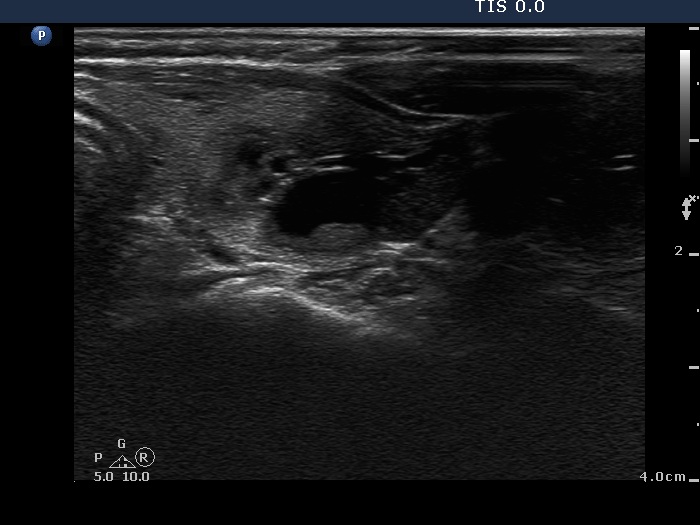

Clinical presentation: A 55-year-old woman was referred for aspiration cytology. She has a right lobectomy 10 years ago. At that time, a relatively small cystic nodule was already in the left lobe which was not operated. She noticed a lump in the left thyroid several weeks before the present examination.

Ultrasonography. There was no parenchyma in the right the thyroid bed. The left lobe was minimally hypoechogenic and had a large, multichambered cystic nodule. There were both hyperechogenic lines and granules within the dorsal wall of the cystic areas. The solid part was moderately hypoechogenic.

Comment. Most of the hyperechogenic figures correspond to posterior back wall enhancement. There were a few colloid crystals within the cystic fluid.